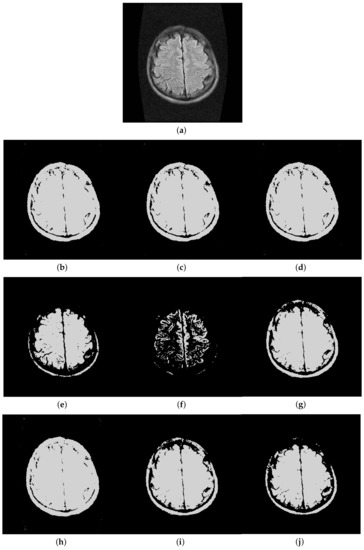

Furthermore, to make purposeful yet effective comparison for the segmentation ability, results of the proposed method are respectively compared with 1D Fisher, 1D maximum entropy, 1D cross entropy, 1D Tsallis entropy, fuzzy entropy, 2D Fisher, 2D maximum entropy and 2D cross entropy. All the original images and segmented results are shown in Figures 4–13.

5.2. Visual Evaluation of the Segmented Image

The qualitative performance of the proposed method and the contemporary methods are given in Figure 4, Figure 5, Figure 6, Figure 7, Figure 8, Figure 9, Figure 10, Figure 11, Figure 12 and Figure 13, respectively. The original images are shown in Figure 4a, Figure 5a, Figure 6a, Figure 7a, Figure 8a, Figure 9a, Figure 10a, Figure 11a, Figure 12a and Figure 13a. The segmented images of the same by 1D Fisher, 1D maximum entropy, 1D cross entropy, 1D Tsallis entropy, fuzzy entropy, 2D Fisher, 2D maximum entropy, 2D cross entropy and the proposed method are shown in Figure 4b–j, Figure 5b–j, Figure 6b–j, Figure 7b–j, Figure 8b–j, Figure 9b–j, Figure 10b–j, Figure 11b–j, Figure 12b–j and Figure 13b–j, respectively. According to the segmented images, 1D Tsallis entropy method has the best segmentation effect among all of the 1D histogram based thresholding methods. For some test images, the segmented result is even better than a portion of 2D histogram based thresholding method. Basically, all of the 2D histogram based thresholding methods have the better segmentation effect than corresponding 1D histogram based thresholding methods. Although 2D maximum entropy can make a great effect for four test images, for all of the 10 test images, its effect is not very good. The experiment shows that the MCBA based 2D Tsallis entropy algorithm provides the best thresholding performance among all methods being compared.

Figure 8. Segmented results of Magnetic Resonance Imaging (MRI) image: (a) original image; (b) 1D Fisher; (c) 1D cross entropy; (d) 1D maximum entropy; (e) 1D Tsallis entropy; (f) fuzzy entropy; (g) 2D Fisher; (h) 2D cross entropy; (i) 2D maximum entropy; (j) proposed method.